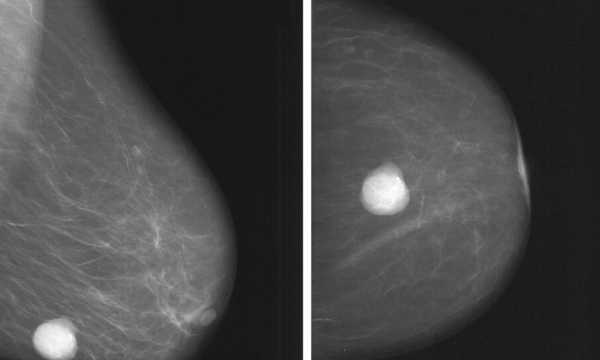

Mammografia rezonansu magnetycznego jest nowoczesną, nieinwazyjną procedurą medyczną, która obecnie stanowi jedną z najlepszych metod obrazowych w diagnostyce zmian piersi. Badanie przeprowadzane jest przy wykorzystaniu pola magnetycznego oraz fal radiowych i pozwala na uzyskanie obrazu gruczołu piersiowego bez udziału szkodliwego promieniowania jonizującego.

W porównaniu z innymi metodami radiologicznymi rezonans magnetyczny piersi cechuje się bardzo wysoką czułością w wykrywaniu raka piersi (często sięgającą 90% i więcej u pacjentek z wysokim ryzykiem lub bardzo gęstą tkanką gruczołową). Z kolei skuteczność klasycznej mammografii (wykrywalność/czułość) jest zwykle znacznie wyższa niż 10–45% i zależy m.in. od wieku i gęstości piersi: u wielu kobiet sięga kilkudziesięciu–kilkunastu procent powyżej tej wartości, natomiast w bardzo gęstych piersiach może być istotnie niższa.

Dużym atutem MRI jest zdolność wykrywania drobnych nieprawidłowości o wielkości około 2 mm, co pozwala na wczesne zobrazowanie zmian bezobjawowych, często niewidocznych w klasycznej mammografii i USG. Badanie zwykle wykonuje się z dożylnym podaniem środka kontrastowego zawierającego gadolin.

Badanie MR piersi pozwala na wykrywanie zmian nowotworowych nawet w tkance o dużej gęstości, gdzie klasyczna mammografia może być mniej czuła

Mammografia MR oferuje istotne korzyści w wczesnym wykrywaniu raka piersi, w tym wysoką dokładność w identyfikowaniu zmian, które mogą nie być widoczne przy użyciu tradycyjnych technik, zwłaszcza u kobiet z gęstym gruczołem piersiowym oraz u pacjentek z wysokim ryzykiem genetycznym. Jest metodą uzupełniającą wobec mammografii rentgenowskiej i USG, a nie ich zamiennikiem. Klasyczna mammografia pozostaje podstawą badań przesiewowych w populacji ogólnej.

MRI a mikrozwapnienia (DCIS)